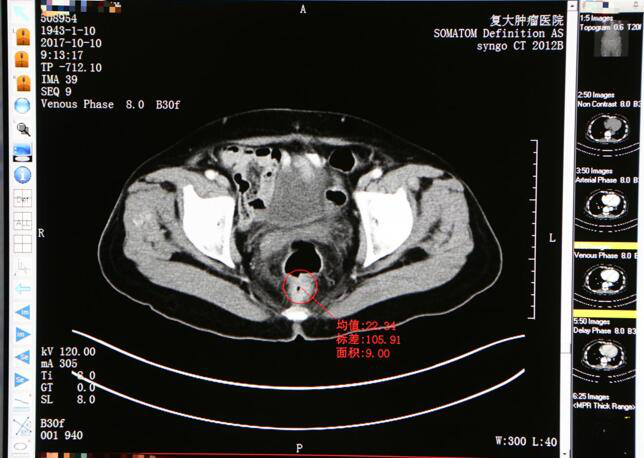

Снимок КТ до лечения

В больнице Фуда сосудистая интервенционная терапия проводится под руководством инструментов визуализации, во время проведения КТ или УЗИ катетер вводится в кровоснабжающую артерию опухоли и затем вводит лекарство. Поскольку внутри опухолевых капилляров небольшие отверстия, лекарственная микросфера может проникать в опухоль через такие отверстия, но не может проникать в нормальные сосуды. Локальная концентрация лекарственного средства, накопленная в краткосрочной перспективе после интервенционной химиотерапии, значительно выше, чем после системной химиотерапии, что дает сильный лечебный эффект, избегая многочисленных побочных эффектов, вызванных системной химиотерапией. Наконец, никаких существенных побочных эффектов не произошло.